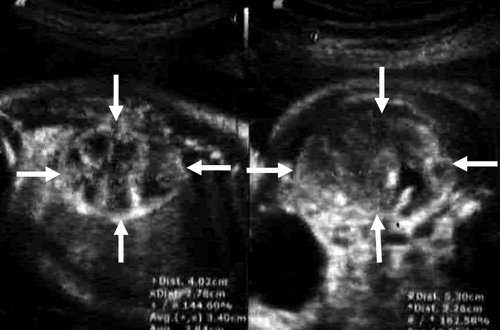

Результаты исследования: размеры плода пропорциональные, соответствуют менструальному сроку беременности. При эхокардиографии особенностей строения сердца у плода не выявлено. При оценке органов мочевыделительной системы обнаружено следующее: правая почка плода нормальных размеров и структуры. Левая почка увеличена до размеров 53х38х46 мм при 95-м процентиле нормативных для срока значений 43х24х23 мм [4] (рис. 1). В структуре почки, преимущественно в верхнем и среднем сегментах, определяется округлое образование без четких контуров, средней эхогенности, приблизительные размеры его 50х35х35 мм. При цветовом допплеровском картировании в образовании визуализируется обширная сосудистая сеть. При допплерометрии индексы сосудистой резистентности (рис. 2) в разных участках образования варьируют в широких пределах (от 0,49 до 0,77).

Рис. 1. Почки плода в режиме 2D. Видна разница в эхографической структуре. Границы почек обозначены стрелками.

При ультразвуковом исследовании в пренатальном периоде опухоль определяется как округлое образование, как правило, больших размеров, без четких контуров. Разница в акустической плотности интактной почечной паренхимы и опухолевой ткани может создавать эффект границы, которая глазом будет восприниматься как капсула. В большинстве случаев при беременности, осложненной возникновением мезобластической нефромы, регистрируется многоводие. Сочетанные изменения в других органах и системах плода встречаются редко.

В представленном клиническом наблюдении диагноз опухоли почки был поставлен нами практически сразу и не вызывал сомнения, поскольку стандартный протокол ультразвукового скринингового исследования во II и III триместрах беременности требует описания почек и мочевого пузыря. Почки оцениваются в поперечном и продольном сечениях с использованием при необходимости цветового допплеровского картирования (рис. 3, а, б). В данном случае почки плода располагались в типичном месте, но обращали на себя внимание значительная разница в размерах и необычная структура одной из почек (см. рис. 1). В 2D режиме границы опухоли четко не визуализировались, но при использовании технологии VCI (объемное контрастное изображение) можно было более точно определить ее контуры (рис. 4).

а) Поперечное сканирование. Переднезадний размер почек обозначен стрелками.